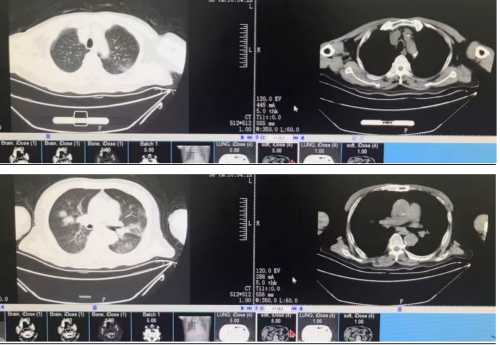

2025-12-04 胸部CT: